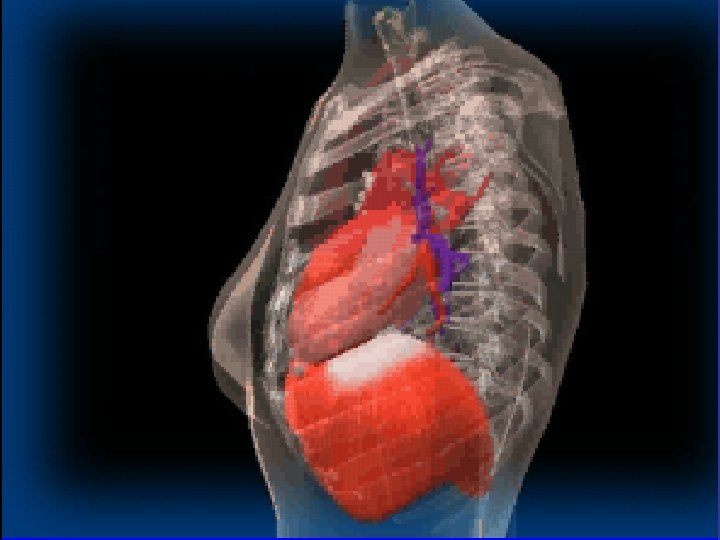

Right ventricular enlargement